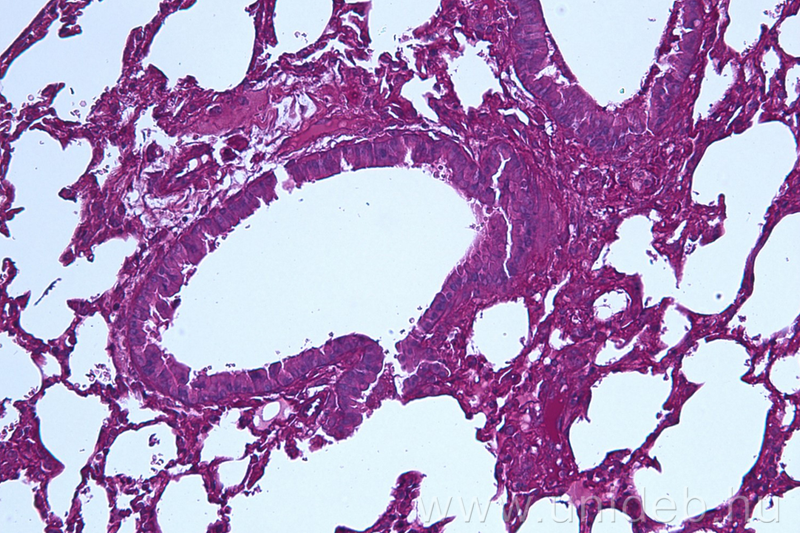

A Szentesi Péter által irányított tudóscsoport bebizonyította, hogy a PAF képes leküzdeni a tüdőben az Aspergillus gomba által okozott betegségét. Az egerekkel végzett tesztek során kiderült, hogy a PAF növelte az állatok túlélését és csökkentette a tüdejükben jelenlévő gomba mennyiségét.